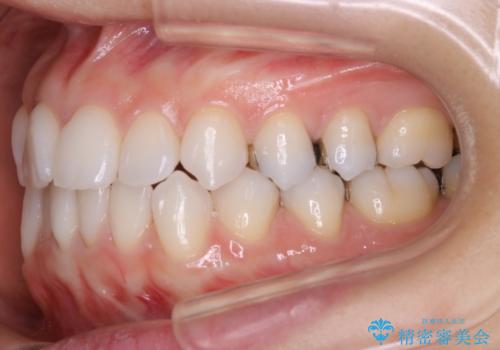

- 前歯のガタつき改善を主訴にご来院されました。

ガタつき自体は軽度で、奥歯の噛み合わせのズレもほとんどなかったため、非抜歯でマウスピース矯正装置を選択しました。

歯列の幅の拡大と歯を小さくする調整を行うことで並べるスペースの確保を行いました。この方法は、ガタつきをとりたいところに直接スペースを作ることができるので治療期間を短縮することができ効率的です。